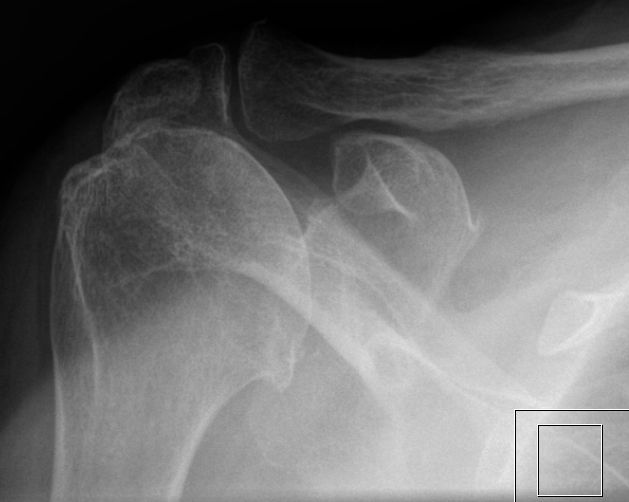

82-jährige Frau mit subduralem Haematom nach Sturz. Alte komplette Rotatorenmanschettenruptur mit Atrophie des Musculus supraspinatus und infraspinatus. Luxationsstellung des rechten Humeruskopfes nach kranial mit weitestgehender Resorption sowohl des akromialseitigen Anteilers des Akromioklavikulargelenkes als auch das Akromion selbst. Der Subakromialraum ist nicht nur aufgebraucht, sondern wird auch nach kranial durch die Schliffsklerosen verlagert. Omarthrosis deformans ohne Anhalt für okkulte Frakturen, inhomogene Verdickung der Gelenkkapsel.Klinisch chronische Schmerzen, Elevation bei 30° schmerzhaft behindert.